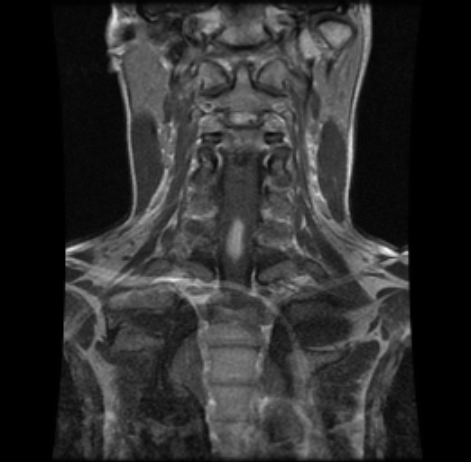

MRI of the cervical and thoracic spine showed a diffuse, intramedullary abnormal signal extending from the medulla down to approximately the mid-thoracic level. There was swelling in portions of the spinal cord, particularly in the lower cervical cord where there was contrast enhancement (Figure 1 [Fig. 1], Figure 2 [Fig. 2], Attachment 1 [Att. 1]). The MRI of the brain was normal.

Figure 2: MRI of the cervical spine, coronal view: contrast enhancement in the lower cervical cord